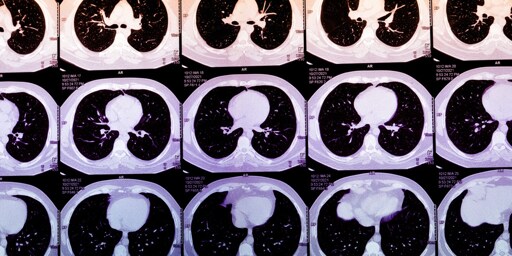

Last year, an estimated 20 million Americans had chest CT scans done, after an event like a car accident or to screen for lung cancer. Frequently, they show evidence of coronary artery calcium (CAC), a marker for heart attack risk, that is buried or not mentioned in a radiology report focusing on ruling out bony injuries, life-threatening internal trauma, or cancer.

Coronary artery calcium can often be spotted on chest CTs, and its concentration can be subjectively described. Normally, quantifying a person’s CAC score involves obtaining a heart-specific CT scan. Algorithms that calculate CAC scores from routine chest CTs, however, could massively expand access to this metric. In practice, these algorithms could then be deployed to alert patients and their doctors about abnormally high scores, encouraging them to seek further care. Today, the footprint of the startups offering AI-derived CAC scores is not large, but it is growing quickly. As their use grows, these algorithms may identify high-risk patients who are traditionally missed or who are on the margins of care.